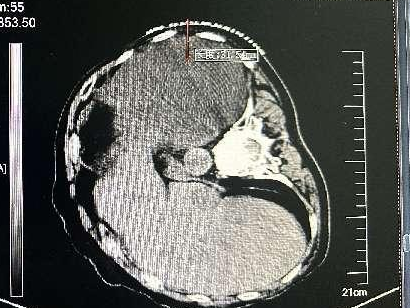

近年来,贵州航天医院各科室紧跟医学前沿,不断强技术、补短板,大力开展新技术、新项目,完成了许多高精尖、高难度、本地区“首例”的技术,填补了医院医疗技术空白,满足了群众日益增长的医疗需求。 贵州航天医院呼吸与危重症医学科是贵州省内呼吸疾病治疗规模最大,诊疗项目最全的呼吸疾病品牌科室,呼吸介入技术达到了全国先进水平,在贵州省内处于领先的地位。 本期,我们将为大家带来呼吸与危重症医学科特色技术——内科胸腔镜技术诊断和治疗胸腔疾病。 案例分享 患者苟某某,因劳累、气促,不明原因胸腔积液在某县一医院采取反复抽水等治疗手段效果不佳,当地医院考虑到患者年龄大(77岁),基础疾病较多,病情复杂,结合当地诊疗水平能力情况,建议转到上一级医院诊治,通过我院与该院建立的呼吸专科联盟绿色通道转入了我院。 患者入院后,呼吸与危重症医学科第一时间复查胸部CT,提示:右肺中叶、左肺感染,纤维化灶,左侧中量胸腔积液,右后侧胸膜轻度增厚,心包少量积液;并完善心电图、血常规、凝血功能、生化指标等术前检查。经科室专家团队集体讨论,得出患者左侧胸腔积液可能原因:结核?恶性?其他?冠心病、心功能不全、高血压病3级(高危组)、陈旧性肺结核复发?肺部感染;为进一步明确诊断,在充分评估、做好术前准备及应急预案、与患者及家属沟通的情况下,决定为患者进行内科胸腔镜检查术。 科室在患者入院第3天便实施了内科胸腔镜检查术,经检查取活检,病理不排除胸膜间皮瘤,送遵义医科大学附属医院病理会诊后诊断:胸膜间皮瘤。明确诊断后,科室专家团队为患者制定了个体化的治疗方案,患者病情很快得到有效控制,最终满意出院。半年后,医院通过电话回访,患者病情稳定,生活质量明显改善。 什么是内科胸腔镜 内科胸腔镜(medical thoracoscopy,MT)是一项微创诊断和治疗胸腔疾病的重要技术。主要应用于无创方法不能确诊的胸腔积液和胸膜疾病,通过局部麻醉后在胸壁做一个小切口,插入胸腔镜,直接观察胸膜、肺表面、纵隔等部位的病变情况,可进行活检、粘连松解及胸膜固定等操作。具有创伤小、恢复快、诊断准确性高等优点。 内科胸腔镜原理 内科胸腔镜是一项利用现代光学技术和成像技术的侵入性操作技术,应用电子支气管镜、硬质或软硬结合(半硬)的胸腔镜的一种电子内窥镜,末端装有连接着显示屏的微型摄像头。通过胸壁1-2cm左右的小切口,将内科胸腔镜及专用器械(戳卡套管)通过小切口进入胸腔,微型摄像头将胸腔内的情况投射到显示屏幕上,医生可以通过镜头全面、直观地观察患者胸腔内情况,了解胸膜病变确切位置和形态改变,还可对胸膜上的病变进行活检及治疗的操作技术,安全、微创、几乎无痛地“揭秘”不明原因的胸腔积液。 内科胸腔镜技术优势 (一)安全性高:仅需局部浸润麻醉,并发症发生率相对较低,对患者的身体条件要求较低。 (二)操作简便:操作时间短,痛苦少,患者耐受好。 (三)微创性:切口小,对患者身体损伤小,术后疼痛轻,恢复快。 (四)高分辨率成像:清晰显示胸腔内细微病变,提高诊断准确性。 (五)可直视操作:直接观察病变,进行精准活检和治疗。 (六)适用范围广:可用于不明原因胸腔积液、胸膜疾病、肺部疾病等的诊断和治疗。 (七)费用低:与外科胸腔镜比较费用低廉。 内科胸腔镜技术是贵州航天医院呼吸专科和呼吸介入诊疗优势的一部分,在2016年率先开展了内科胸腔镜技术,年手术量约100余例,已建立了快速、精准、规范、有效的一体化诊疗服务体系。目前呼吸与危重症医学科内科胸腔镜技术广泛应用于不明原因胸腔积液、气胸、脓胸的诊断和肺癌、弥漫性恶性胸膜间皮瘤等的分期,恶性或复发性胸腔积液、早期脓胸、自发性顽固性气胸的治疗。 镜下常见表现:单发或多发结节、灰白色弥漫性粟粒样结节、胸膜充血、水肿、胸膜增厚及纤维分隔或粘连带形成。 诊断方面: 胸腔积液的病因诊断。内科胸腔镜对恶性胸腔积液的诊断率可高达90%以上,胸腔镜对结核性病变诊断率极高,几乎达到96%以上。 腺 癌 恶性淋巴瘤 软骨肉瘤胸膜转移 滑膜肉瘤胸膜转移 结核性胸膜炎 治疗方面: 脓胸 肺大泡 贵州航天医院 呼吸与危重症医学科学科带头人 廖江荣 国务院政府特殊津贴专家 二级教授 主任医师 贵州航天医院副院长 国家级学术任职: 第二届中国医药教育协会介入微创专业委员会呼吸分会副主任委员 中国抗癌协会肿瘤微创治疗专业委员会常务委员 中国防痨协会结核病转化医学专业分会常务委员 第一届中国人体健康科技促进会呼吸介入专委会常务委员 中国医疗保健国际交流促进会结核病学分会第三届委员会常务委员 中国抗癌协会肿瘤微创治疗专业委员会粒子治疗学组第四届委员会委员 中华医学会结核临床专业委员会内镜介入委员 中华医学会放射学分会第十五届委员会介入学组呼吸系统介入专业委员会委员 北京健康促进会中青年专家委员会胸部疾病精准活检分委会副主任委员 中国医师协会介入医师分会第二届委员会肿瘤消融专业委员会委员 中国结核病防治综合质量控制专家指导委员会委员 亚洲冷冻治疗学会常务委员 世界内镜医师协会呼吸内镜协会常务理事 内镜临床诊疗质量评价专家委员会委员 “西部呼吸介入联盟”副理事长 专业擅长: 贵州航天医院 呼吸与危重症医学科简介 贵州航天医院呼吸与危重症医学科以呼吸危重症和介入呼吸病学为强力推手,以肺部感染性疾病及肺癌、肺小结节的早期精准诊疗、慢性呼吸疾病康复治疗为特色,以人才团队建设为核心的科室发展模式,现已成为省内呼吸疾病治疗规模最大,诊疗项目最全的呼吸疾病品牌科室。是贵州省医学重点学科、临床医学重点专科建设单位,遵义市首批呼吸重点学科、重点专科建设单位。是国家卫健委能力建设和继续教育肿瘤微创介入建设中心、贵州省县级医院微创介入培训中心、遵义市呼吸疾病临床医学中心。是国家呼吸医疗质量控制与管理哨点医院、遵义市呼吸内科专业医疗质量控制中心。是中国医药教育协会介入微创呼吸分会呼吸介入技术培训中心单位;国家卫健委海医会呼吸分会ROSE专委会“诊断性介入肺脏病学快速现场评价”培训基地;中国肺癌防治联盟“贵州航天医院肺结节诊治”分中心,中国人体健康科技促进会呼吸介入技术培训基地,贵州省中西医结合会呼吸学分会呼吸介入专委会主委单位。 基本情况 平均每年开展气管镜诊疗约4000例,经皮肺穿刺介入诊疗近千例,开展的项目包括经支气管镜(软、硬)下冷冻、氩气刀、高频电刀、球囊扩张、支架置入、超声内镜诊疗等气道介入诊疗技术,经皮肺穿刺活检及肿瘤消融术(微波、冷冻)、ROSE技术、内科胸腔镜诊疗及经血管介入诊疗技术,且多项呼吸介入诊疗技术在省内处于领先水平。 诊疗范围 航天医院呼吸专科擅长:致力于呼吸系统感染性、疑难性疾病的介入快速精准诊疗;肺癌与肺小结节早期精准诊疗水平项目提升。擅长于呼吸系统(肺)疑难病的诊断及危重病的救治,尤其在肺癌、肺小结节的早期诊断;肺癌综合靶向治疗;肺结核综合诊疗;肺部疾病的介入诊疗在省内处于前沿水平。 咨询热线 (一)呼吸与危重症医学科一病区 医生办公室:27677317 护士站:28614217 (二)呼吸与危重症医学科二病区 医生办公室:28691274 护士站:28690442 (三)呼吸与危重症医学科三病区 医生办公室:28692417 护士站:28690461 (四)呼吸与危重症医学科四病区 医生办公室:28616402、27677582 护士站:28614987、27677862